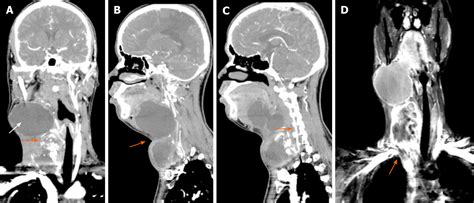

The *carotid* arteries are crucial for diagnosing and treating conditions such as carotid artery disease, which can lead to stroke if left untreated. Medical professionals often use imaging techniques such as ultrasound, CT angiography, and MRI to assess the health of the *carotid* arteries and detect any blockages or narrowing.

MRI is an imaging technique that uses magnetic fields and radio waves to create detailed images of the body's internal structures. It is often used to assess the health of the *carotid* arteries and detect any blockages or narrowing. MRI can also be used to visualize the *jugular* veins and detect any abnormalities.